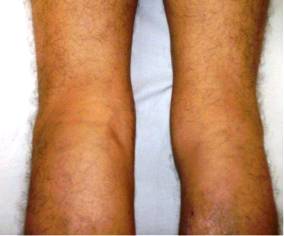

A la exploración se observan signos inflamatorios de la rodilla y se palpa zona de induración de más menos 10 cm x 8 cm, de consistencia dura, adherida a planos profundos en proyección de la región posterior de la pantorrilla. Aumento de la vascularización de la pierna izquierda.

Obsérvese aumento de volumen de la rodilla izquierda y pantorrilla, así como de la vascularización de la pierna, la cual se extiende a la fosa poplítea y a lo largo de toda la pierna Imágenes 1, 2 y 3

Imagen 1. Aumento de volumen de la rodilla y pantorrilla izquierda, cambios en la red venosa superficial